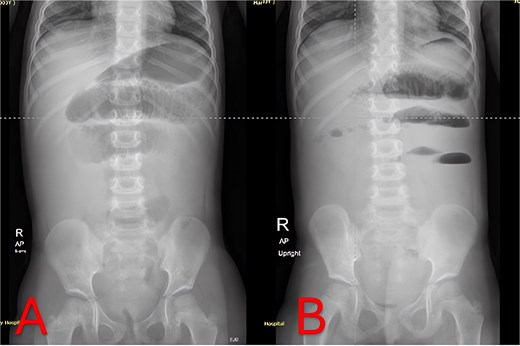

Plain abdominal radiographs revealed centrally dilated small-bowel loops with paucity of distal gas (Fig. 1A) and multiple air–fluid levels without free subdiaphragmatic air (Fig. 1B), consistent with mechanical small-bowel obstruction. Initial management, including nasogastric decompression, nil per os (NPO) status, and intravenous ceftriaxone (75 mg/kg once daily) plus vancomycin (15 mg/kg every 6 hours), failed to improve radiographic findings after 24 hours (Fig. 2A and B), prompting further imaging.

Twenty-four-hour follow-up abdominal X-rays. (A) Supine view 24 hours postadmission with persistent small-bowel distension. (B) Upright view 24 hours postadmission confirming ongoing air–fluid levels and no colonic gas.